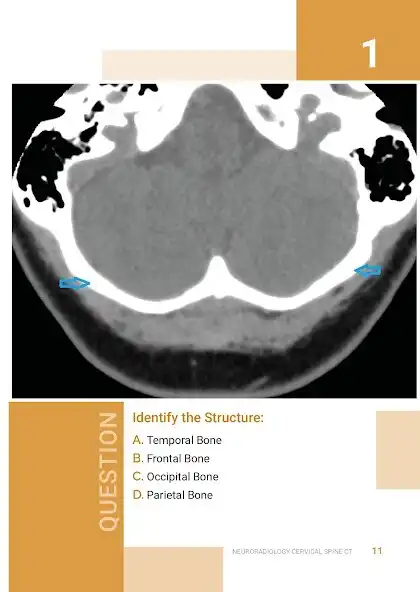

This is an exciting and easy to use Atlas / Quiz of NORMAL Neuroradiology, and attempts to bridge the gap between Anatomy atlases and Radiology atlases. It focuses on the needs of neurology residents and medical students, but anyone who is interested in the radiological anatomy of the brain will find it useful. Using these books as android apps is also reducing production cost , saving printing cost (and trees too in case you like trees). But these same books are also available elsewhere as print versions, but for higher cost.

The objective of the How to Read a Normal Scan series is to familiarize you with NORMAL anatomy as seen on MRI scans and CT scans before memorizing what Hallevorden Spatz or Blah

Blah looks like (sure enough in your Board exam they will want you to identify Blah Blah that no one has seen in 500 doctor years). My hope is, that after reading these books, at the very least you can point out structures on a normal scan and identify exactly what they are. And it is not just about avoiding the embarrassment of ignorance, it is about the sheer satisfaction of knowing what these things are.. If you notice any errors please reach out to me and I will be sure to fix it in the next edition.